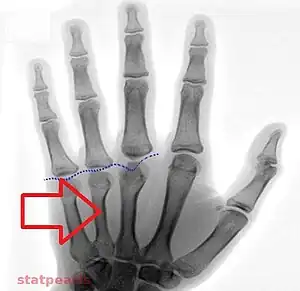

Short 3rd to 5th metatarsals as may be seen in pseudohypoparathyroidism type 1a and 1c

Type 1a Pseudohypoparathyroidism is clinically manifest by bone resorption with blunting of the fourth and fifth knuckles of the hand, most notable when the dorsum of the hand is viewed in closed fist position. This presentation is known as 'knuckle knuckle dimple dimple' sign (Archibald's sign). This is as opposed to Turner syndrome which is characterized by blunting of only the fourth knuckle, and Down syndrome, which is associated with a hypoplastic middle phalanx.

Has a characteristic phenotypic appearance (Albright's hereditary osteodystrophy), including short fourth and fifth metacarpals and a rounded facies. It is most likely an autosomal dominant disorder.[9] It is also associated with thyroid stimulating hormone resistance. Caused by GNAS1 mutation.[10]